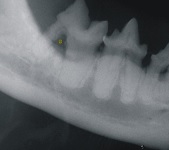

Furcation Defect April 2009-01

The explorer passes under the crown of the 4th premolar tooth and is visible on the inside of the oral cavity (Yellow arrow)